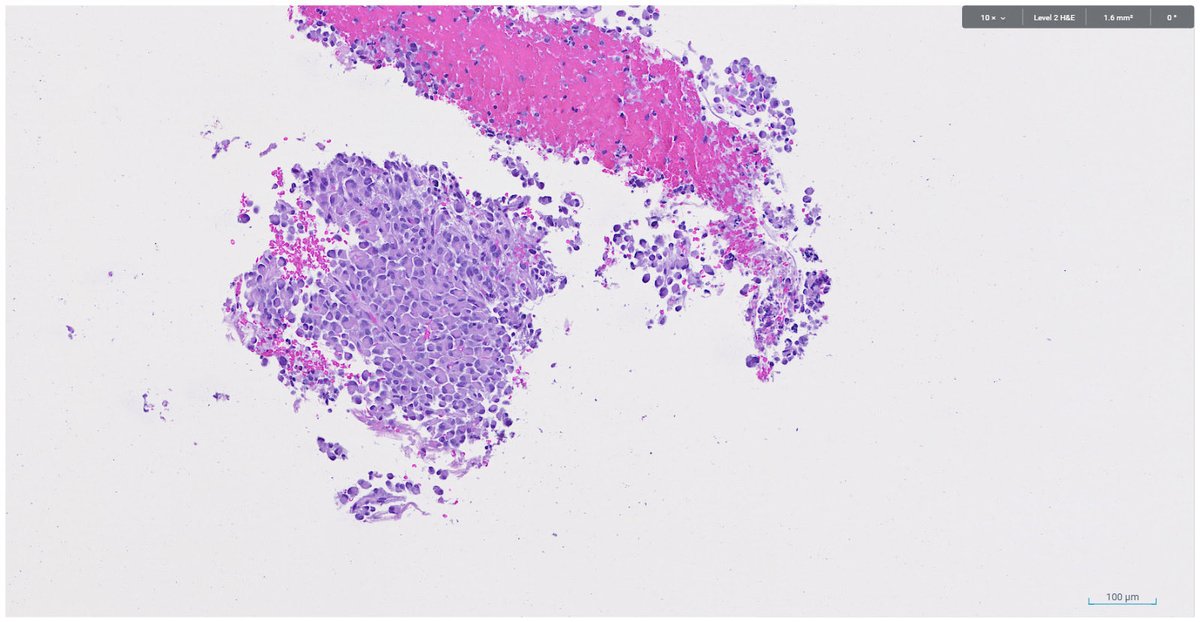

Bread and Butter: It's easy to overlook T4a colorectal carcinoma when mesothelium (indicated) extends up along adipose tissue lobules. In this case, the cancer cells link to the mesothelial cells via inflammation. #umiamipath